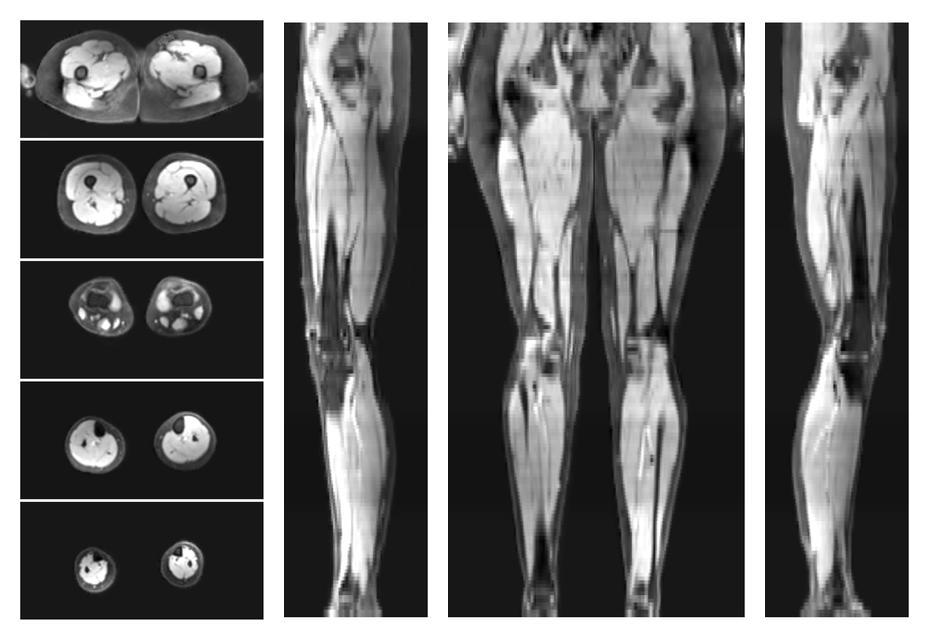

Water only T2 mapping

Multi echo spin echo T2 relaxation time mapping with EPG reconstruction, for information look here».

- Water only signal

- Water only T2 relaxation time

- Mean diffusivity

- Fractional anisotropy

- SNR of the unweighted image